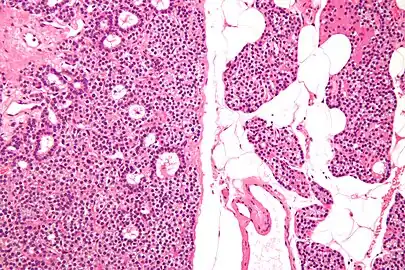

Normal parathyroid gland with prominent adipose tissue is seen on the right of the image.-High magnification -

Intermediate magnification -

Histopatholgical image of parathyroid adenoma in a patient with primary hyperparathyroidism. Hematoxylin and eosin stain. -

Histopatholgical image of parathyroid adenoma in a patient with primary hyperparathyroidism. Hematoxylin and eosin stain. Another view of the same lesion